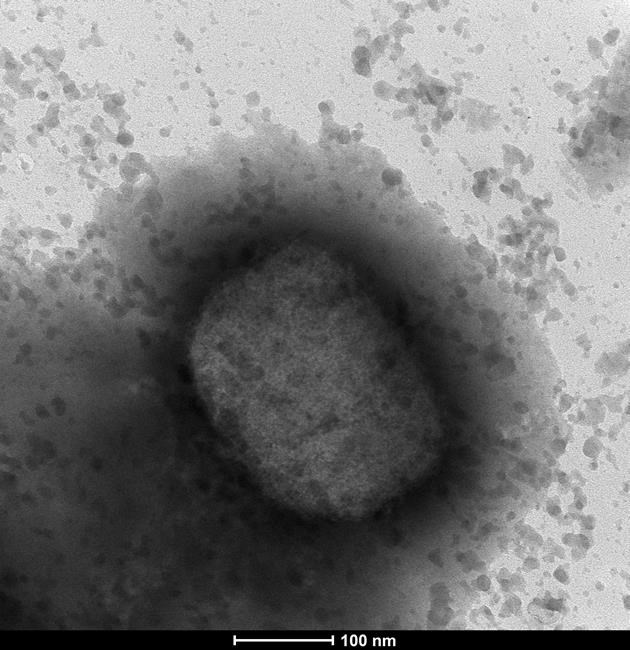

Monkeypox is a rare disease that comes from the same family of viruses that cause smallpox, which the World Health Organization declared eradicated around the globe in 1980.